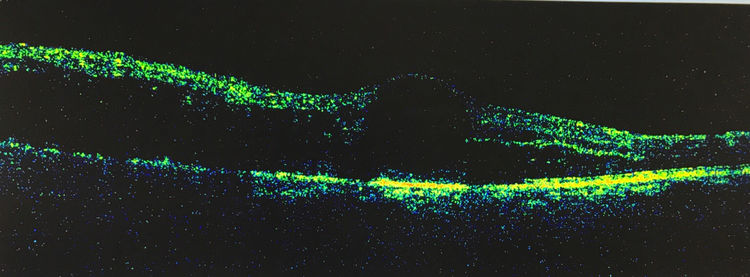

可是当“视网膜静脉阻塞、糖尿病视网膜病变、黄斑病变等来袭时,就会发现黄斑中心凹陷消失,变成了凸起,七拱八翘的像小山丘,这就是眼底常见病"黄斑水肿",视力下降、视物模糊,这时候如果不治疗它就像发面一样慢慢越肿越高……

肿、肿、肿…,现在它的海拔上升到1271µm,怎么样?可以和珠穆朗玛峰媲美吧,是的,它很美,但是你的视力则会急剧下降,平面以下或许就是一个眼前指数或手动,怎么办呢?